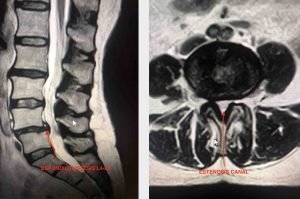

Las sesiones de fisioterapia tampoco mejoraron sus síntomas. Acude a la consulta donde solicitamos una RMN columna lumbar, el resultado una espondilolistesis L4-L5 con estenosis de canal central L4-L5.

Espondilolistesis L4-L5 con estenosis del canal central